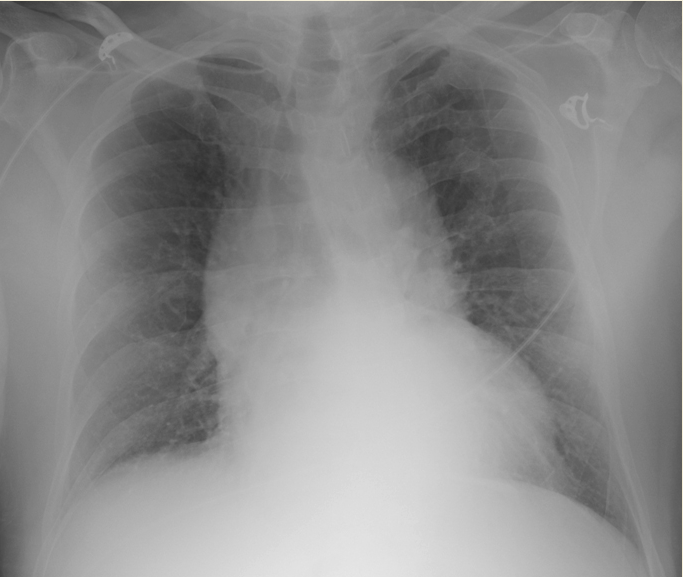

72yo with 4month hx leg swelling & increased abdominal girth. 2-year hx progressive sob. was a sandblaster.

silicosis

give o2